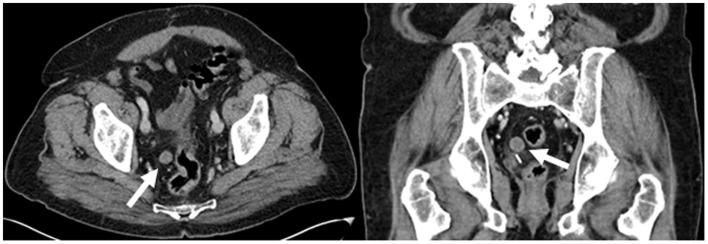

We present the case of a 77-year-old male with a history of prostate cancer. Follow up PET-CT and contrast-enhanced CT demonstrated a small peritoneal loose body or "mouse" in the pelvis. This is an uncommon, benign, asymptomatic finding which is usually incidentally discovered. The significance of being aware of this entity is to distinguish it from metastasis, especially in patients with known abdominal and pelvic malignancies.

我们报告了一例 77 岁男性前列腺癌病史。随访 PET-CT 和增强 CT 显示骨盆内有一个小的腹膜游离体或“鼠标”。这是一种不常见的良性、无症状的发现,通常是偶然发现的。认识到这种实体的意义在于将其与转移区分开来,特别是在已知有腹部和盆腔恶性肿瘤的患者中。